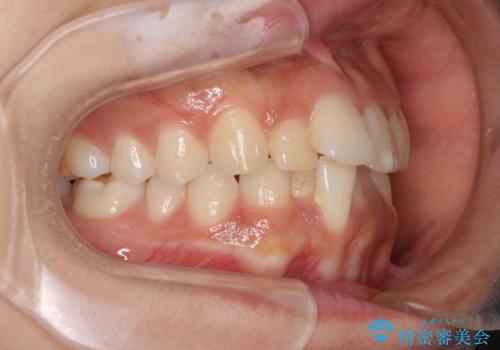

- 飛び出した前歯と全体的なデコボコを気にして来院された患者様です。

大きなトラブルもなく、順調に歯列が整ったため、僅か9ヶ月で装置を外すことができました。